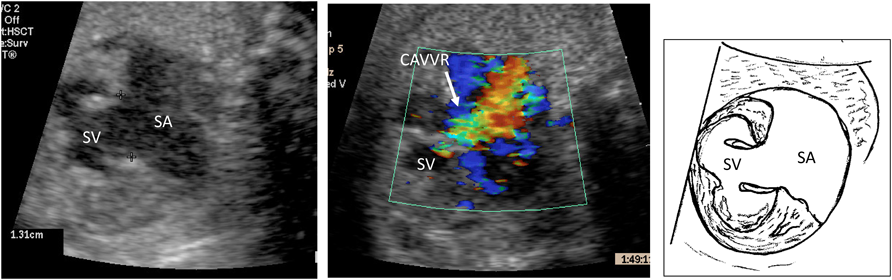

9. 総肺静脈還流異常(Total Anomalous Pulmonary Venous Connection: TAPVC)

TAPVCは四腔断面が一見正常に見えるため胎児診断の難しい疾患である.近年スクリーニング方法(PLAS index20)など)の開発で胎児診断例が増加してはいるが,胎児診断されずいまだに出生後搬送となることの多い疾患である.胎児診断した場合には病型を確認し,特に1型と3型においては垂直静脈の狭窄に伴う肺静脈狭窄がないかどうかの確認が重要である.また共通肺静脈腔の大きさや位置の確認も生後の術式を考える参考となる.肺静脈狭窄がある場合には胎児期からの肺うっ血により出生後肺高血圧を合併する可能性が高くなり予後に影響する21, 22).実際の重度肺静脈狭窄例における肺静脈血流を,正常例と合わせて呈示した(Fig. 7).